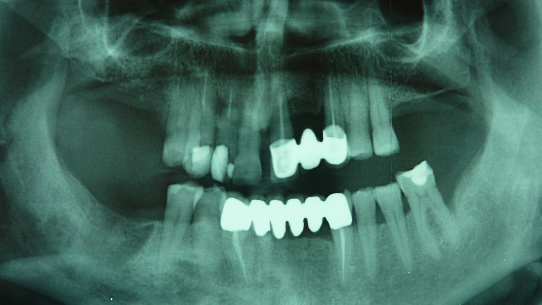

Abbiamo tuttavia osservato un comportamento antitetico tra i pazienti con una normocclusione rispetto ai pazienti malocclusi: infatti i test eseguiti con svincolo occlusale (sia in semplice appoggio che in serramento con rulli di cotone tra le arcate) hanno evidenziato che i pazienti con una buona occlusione o con morso profondo subivano un peggioramento delle loro performances posturali rispetto ai test eseguiti in occlusione abituale, mentre gli stessi test eseguiti su pazienti francamente malocclusi hanno comunque evidenziato un notevole miglioramento rispetto alle analisi condotte in occlusione centrica o in serramento. Va rilevato che per paziente maloccluso in questo studio abbiamo considerato condizioni di importante alterazione dell’allineamento o della forma d’arcata, di riduzione della formula dentaria (assenza di più elementi), di laterodeviazione mandibolare funzionale associata o meno a morso crociato: in generale una condizione di appoggio occlusale insufficiente associato a un alterato rapporto cranio mandibolare (valutato nelle tre dimensioni dello spazio).

(Figg. 3-8)